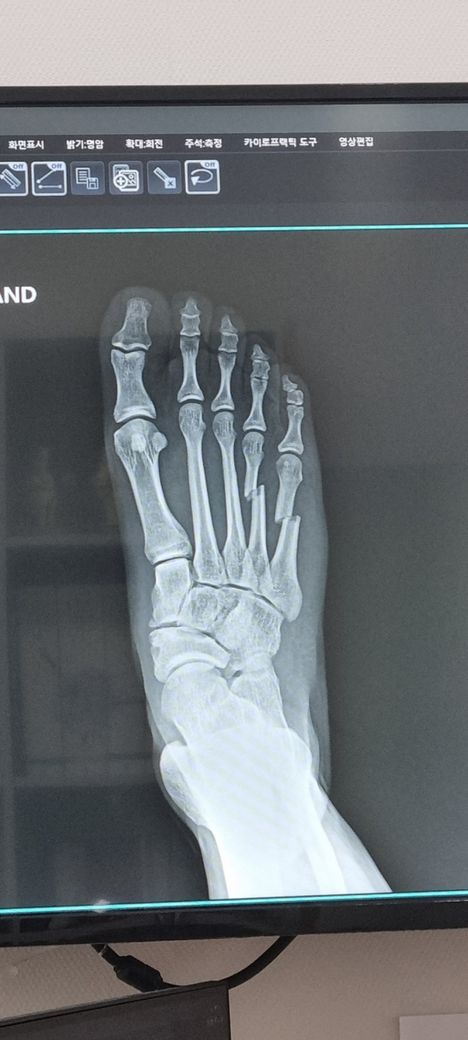

안녕하세요 MMA 스파링도중 발등뼈가 부러졌습니다.

또 아래 사진정도면 신체검사시 감점때문에 그런데 비수술로는 회복이 어려울까요?

• 개개인마다 회복력이나 회복 과정에서 발생하는 여러가지 요인에 의해서 회복에 걸릴 시간이 천차만별로 다르기 때문에 현재로서는 정확하게 알기 어렵습니다. 다만, 일반적으로 수술 후 회복에 있어서는 최소 2-3개월이 소요되는 만큼 12월까지 68일만에 뛸 정도로 회복이 가능하지 못할 가능성이 더 높습니다. 비수술적으로 회복을 하더라도 시간은 오래 걸리는데, 현재 상태에서 뼈가 많이 어긋나 있는데 수술을 하지 않을 경우 회복 기간이 중요할 것이 아니라 걷는 것과 뛰는 기능 자체에 문제가 생길 우려가 있습니다.